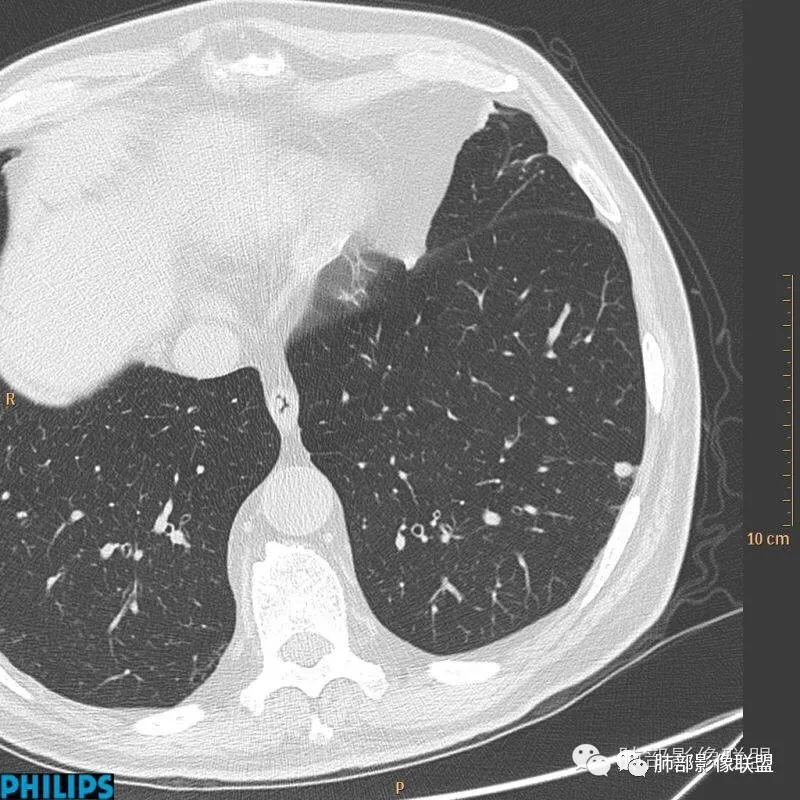

病例二:

以上病例,有什么共同点?1、病灶均位于胸膜下或叶间胸膜下;

2、病灶边缘多平直,大部分呈三角形,部分呈椭圆形;

3、病灶边缘见一条或数条细线与胸膜相连。

正常情况下,肺内淋巴结是不显示的,一般是慢性炎症所致,老年人和吸烟者多见。影像上常见于胸膜或叶间胸膜下,迄今为止,所有的报道均距胸膜或叶间胸膜小于2.0cm以内。也可以表现为与胸膜或叶间胸膜相贴的结节。绝大多数位于中下叶(气管隆突水平以下),上叶也可见到,但较少见。

长径均小于12mm。典型的形状为三角形,也可以为梭形、圆形或椭圆形。诊断的关键在于见到1-5条细线与胸膜、叶间胸膜或静脉相连,有时状如坐落于电路板的“二极管”,但以薄层CT显示为佳。有作者病理对照线状影为小叶间隔,有作者病理对照为淋巴管。其实不矛盾,因为淋巴管走行于小叶间隔内。